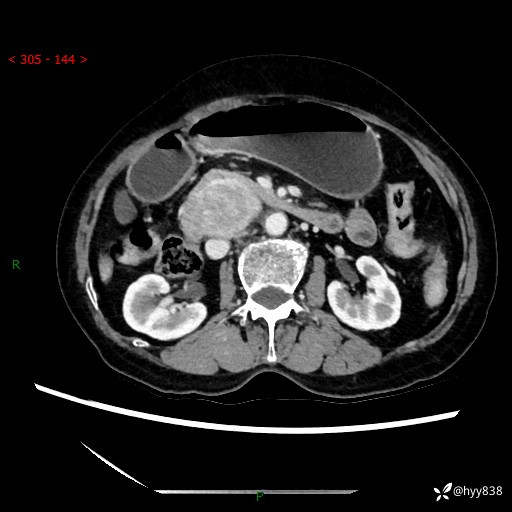

71岁/女,腹痛1月余。腹膜后肿物,间质瘤 VS 副节瘤 VS 平滑肌肉瘤---(有结果)

【患者信息】:71岁/女

【主诉】:腹痛1月余

【检查】:腹部CT增强扫描(外院CT平扫)